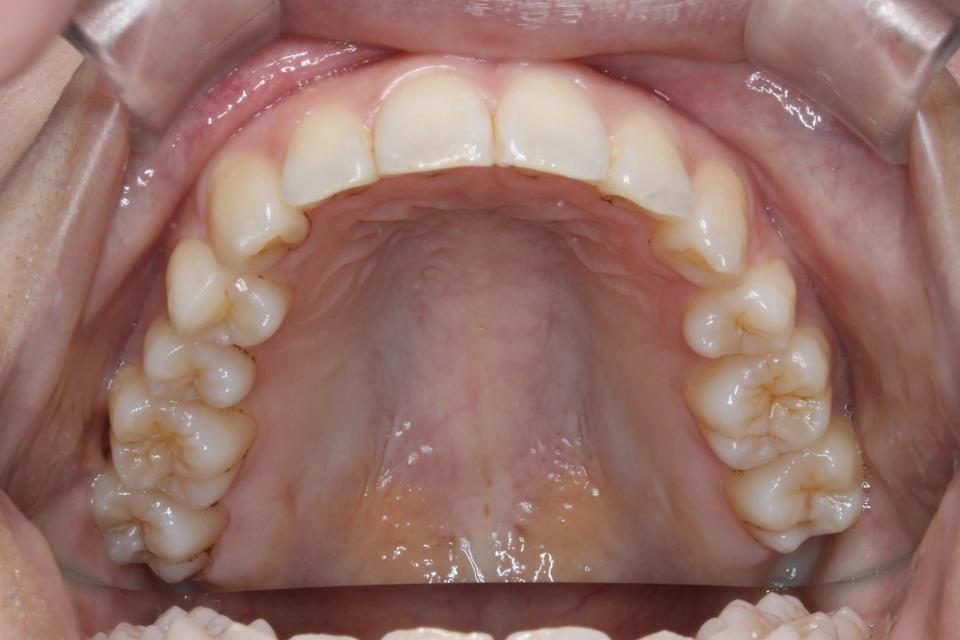

上顎前突(出っ歯)のマウスピース矯正治療例(抜歯あり)

矯正治療前

矯正治療後

20代女性の患者さんです。

歯並びのガタガタと出っ歯気になり矯正治療を始めました。

左上4番目の歯を抜歯して、マウスピース型の矯正治療装置を使用し、歯のやすり掛け(IPR)を行いました。